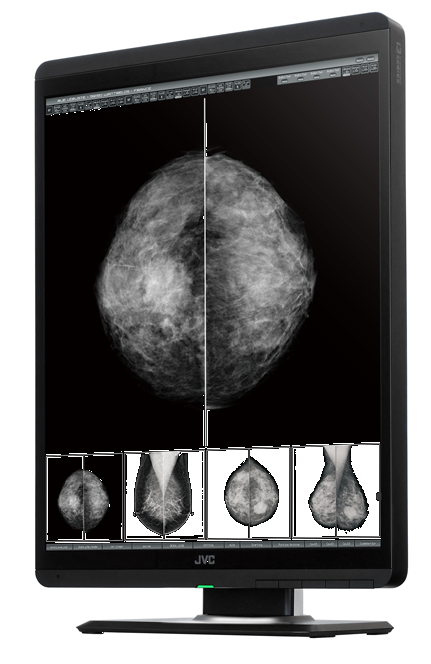

Monitor MS-S500 to następca modelu MS55i2 plus. W porównaniu do swojego poprzednika oferuje on bardzo wysoką jasność maksymalną wynoszącą aż 3000cd/m², gwarantując tym samym bardzo długi czas pracy oraz bardzo wysoki kontrast wyświetlanego obrazu. Jasność po kalibracji wynosząca 1000cd/m² zapewnia ostre i bardzo wyraźne obrazowanie tkanki piersiowej.

Monitor MS-S500 jest fabrycznie kalibrowany do jasności 1000 cd / m2, co czyni go najlepszym rozwiązaniem do ogladania obrazów piersi. Wysoka jasność ekranu monitora radykalnie zwiększa ilość widzianych odcieni szarości, dzięki czemu wykrywalność mikrozwapnień i guzów jest dużo większa.

Wysoki współczynnik kontrastu 2000:1 gwarantuje bardzo wyraźny obraz ułatwiając radiologom interpretację wyników i zwiększając wydajność pracy.